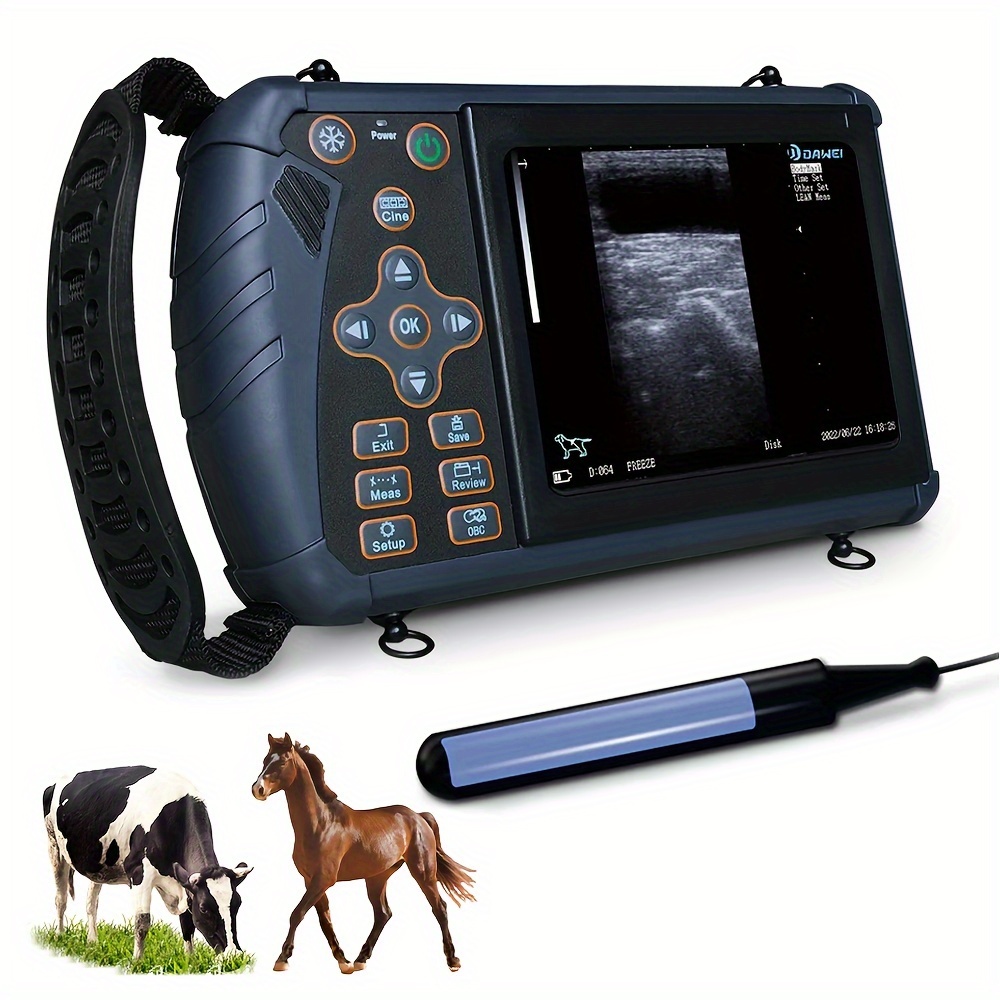

Brand: DAWEI

3.5MHz Probe: Ideal For Ultrasound Imaging And Pregnancy Testing Of Medium-sized Animals Such As Pigs, Sheep, Dogs, Etc

DAWEI-S0 Is A Portable Veterinary Ultrasound (B-ultrasound) Diagnostic Instrument. Its Superior Product Performance And Ergonomic Handheld Design Bring More Convenience To Users During Testing.